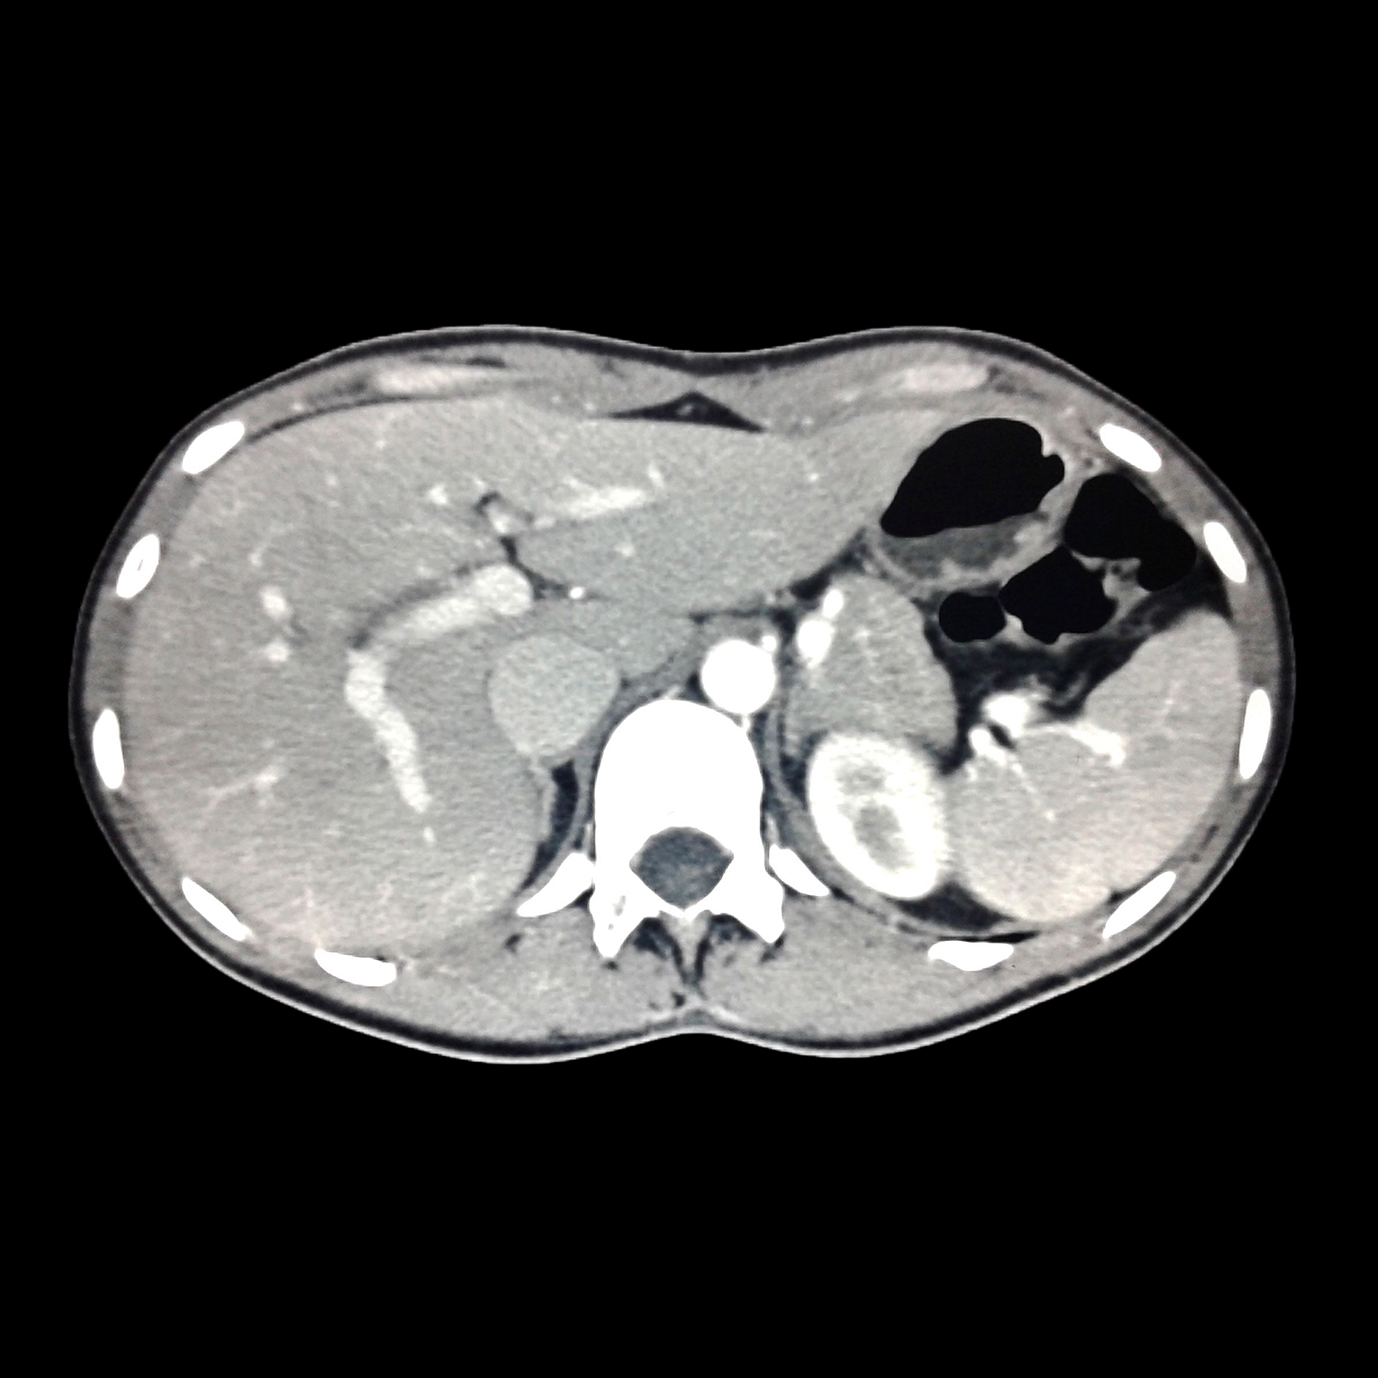

Ejemplos de estudios realizados en nuestra clínica.

con precisión avanzada para un diagnóstico confiable